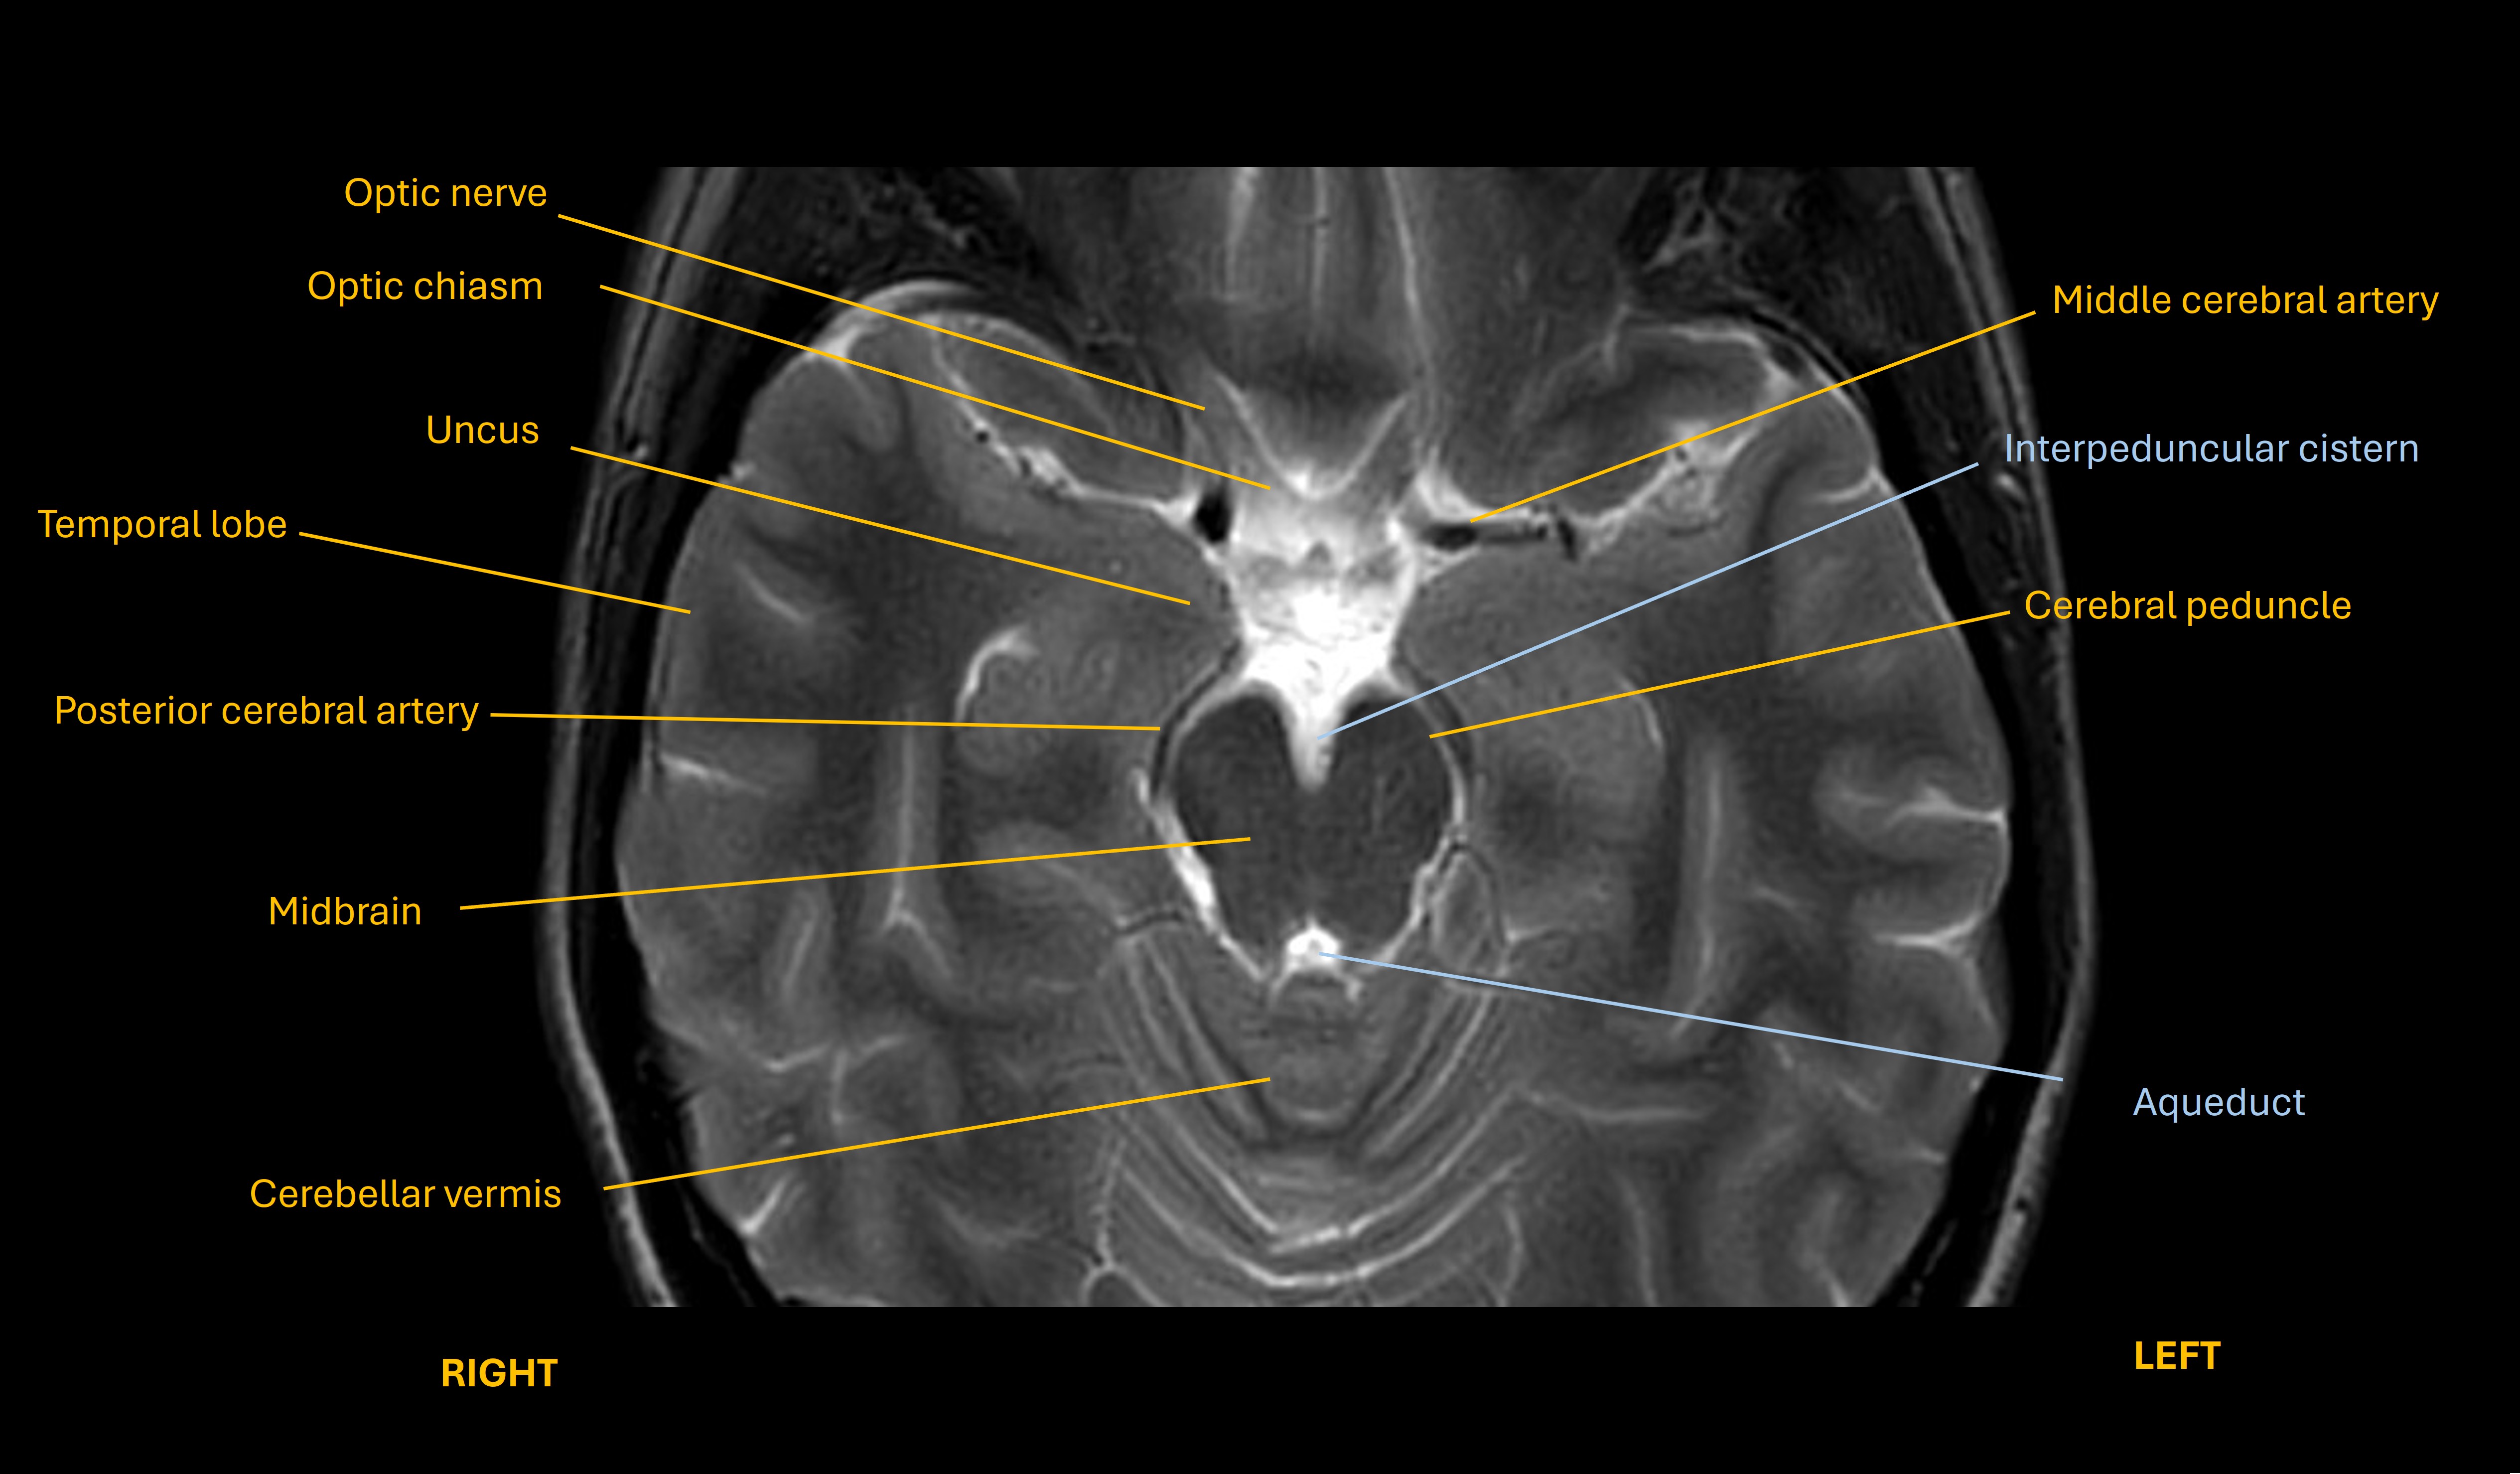

There are many causes of a compressive III palsy, but the chief one in anyone presenting with unconsciousness is herniation of the temporal lobe uncus (see image below) under the tentorium, compressing III. This happens due to anything that causes severe mass effect in the ipsilateral brain above this, for example haemorrhage, massive ischaemic stroke, tumour or oedema due to hypoxia.

Uncus image

In the context this is a very concerning sign, and a rapidly expanding mass lesion in the right hemisphere is a major concern.